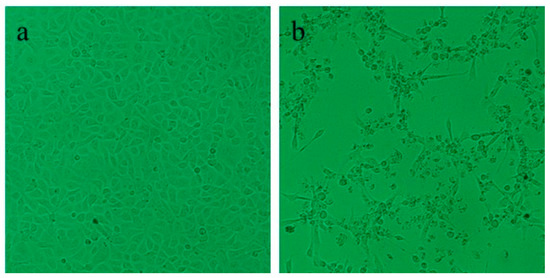

| Subadult | 6 | 429 ± 108 | 0% (0/6) | 0% (0/6) | 0% (0/6) | 0% (0/6) | 0% (0/6) | 0% (0/6) | 0% (0/6) | 0% (0/6) | 0% (0/6) | 100% (6/6) | 100% (2/2) | 0% (0/6) |

| Juvenile | 6 | 40 ± 14 | 33% (2/6) | 0% (0/6) | 0% (0/6) | 0% (0/6) | 0% (0/6) | 0% (0/6) | 0% (0/6) | 0% (0/6) | 0% (0/6) | 100% (6/6) | 100% (3/3) | 0% (0/6) |